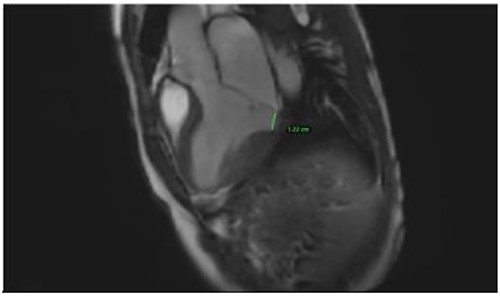

Clinically, both patients complained of worsening palpitations over the last few months with no associated dyspnea or tiredness. A Holter examination recorded 14 444 VES and 212 NSVT, with very similar results in both sisters. The echocardiography revealed a myxomatous Barlow mitral valve with anterior and posterior leaflet prolapse and two regurgitant jets resulting in moderate to severe mitral valve regurgitation as well as mitral annular disjunction in both cases (Figs 1 and 2). A cardiac MRI on a 3 T Lumina Siemens revealed at the mid-left ventricular level, a midwall fibrosis in the midlateral myocardium (Figs 3 and 4) and confirmed a mitral annular disjunction of 12 mm (Figs 5 and 6). Additional findings included a dilated LV with mildly depressed contractility, no visible myocardial scarring, no structural heart disease and a normal sized RV with mildly depressed contractility.